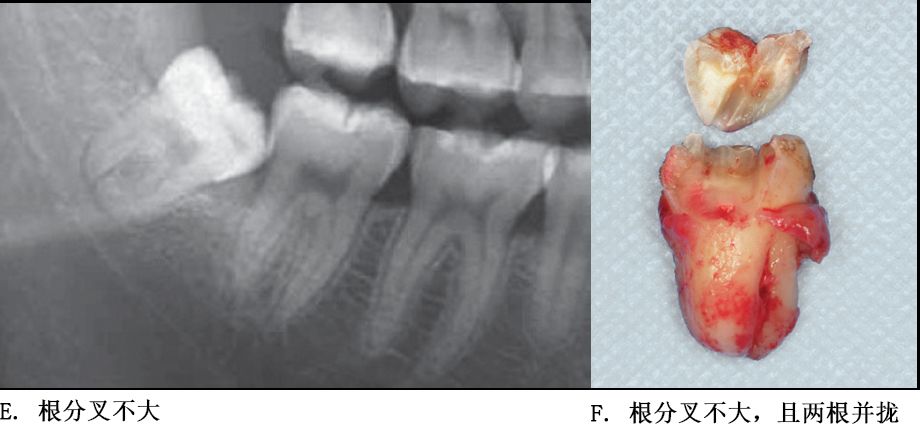

根部阻力较小的智齿形态

单根牙、根分叉不大者、合并根、融合根、特短根、锥形根阻力较小。若根尖区向远中弯曲、无弯曲或根尖未形成,则阻力也较小。